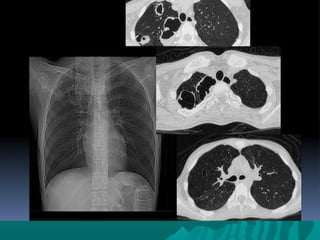

TEM EN TORAXTEM EN TORAX

Indicaciones para examen deIndicaciones para examen de

toraxtorax

Modo en espiral para estudios de rutina deModo en espiral para estudios de rutina de

torax v.g.torax v.g.

Neumonia, tumores, metástasis , linfomaNeumonia, tumores, metástasis , linfoma

anormalidades vasculares entre otrosanormalidades vasculares entre otros

FIBROSIS PULMONARFIBROSIS PULMONAR